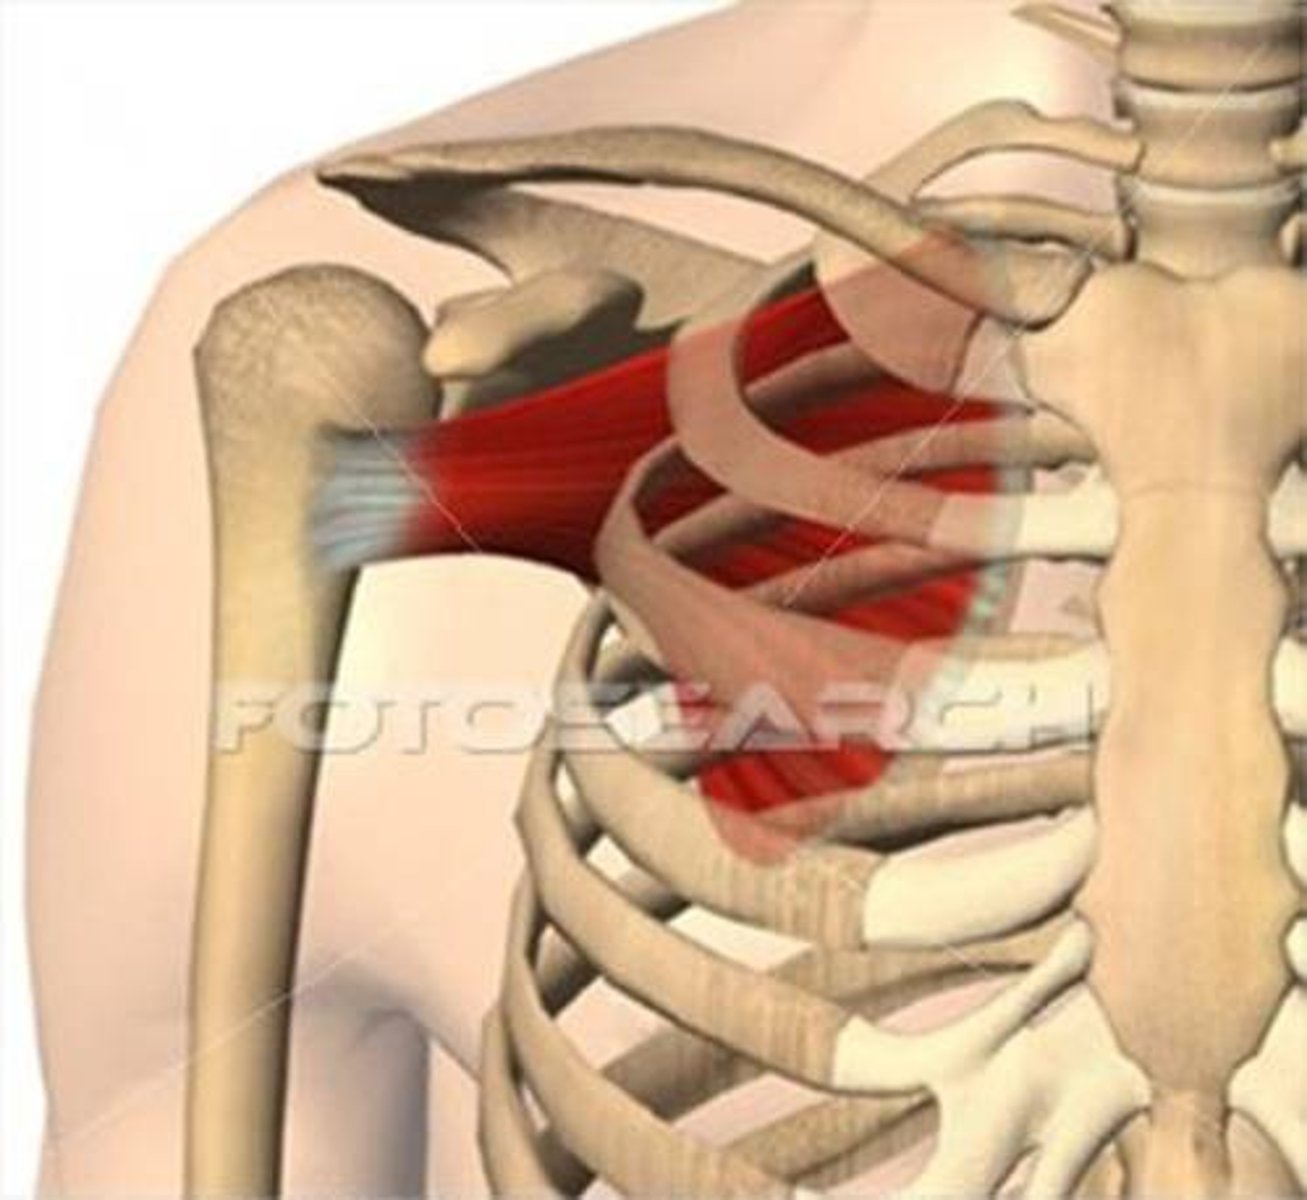

(Rotator Cuff Muscles:) Subscapularis

-Medially rotates arm

-Upper and lower subscapular nerves (C5 - C7)